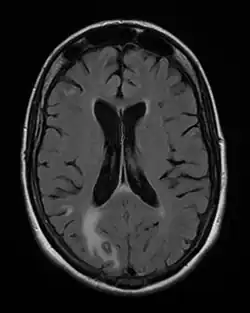

- Toxoplasmosis aguda adquirida o reactivada en el paciente inmunodeficiente, las formas clínicas más graves, incluyendo leucemia, enfermedades del tejido conectivo, los cuales pueden manifestarse en un 40 % de pacientes con sida, por ejemplo.[20] Los pacientes con terapias inmunosupresoras (glucocorticoides, por ejemplo) como para prevenir el rechazo de un órgano trasplantado o el tratamiento de una enfermedad autoinmunitaria, pertenecen a este grupo de alto riesgo.

Otros métodos indirectos incluyen reacciones de fijación de complemento, reacción con colorantes de Sabin y Feldman, pruebas de ELISA y la reacción de hemaglutinación indirecta. Es posible también demostrar la presencia del genoma del parásito con la técnica de PCR, un método importante debido a su alta sensibilidad y especificidad,[24] pues siempre que es positivo confirma el diagnóstico pero si es negativo no siempre lo excluye. El método de detección por PCR se utiliza en el diagnóstico de toxoplasmosis en el líquido amniótico, en el humor acuoso en toxoplasmosis ocular y en inmunosuprimidos.[26] La detección directa del parásito en tejidos infectados puede también resultar difícil, por ejemplo, de placenta o cerebro, incluyendo la fijación de anticuerpos fluorescentes.

De importancia en los casos más graves donde se ven los síntomas más notables, la toxoplasmosis puede confundirse con la leptospirosis,[27] enfermedad de Hodgkin y otros linfomas,[28] encefalitis, mononucleosis, miocarditis, pulmonía (tuberculosis) en inmunocomprometidos y sarcoidosis.[20]